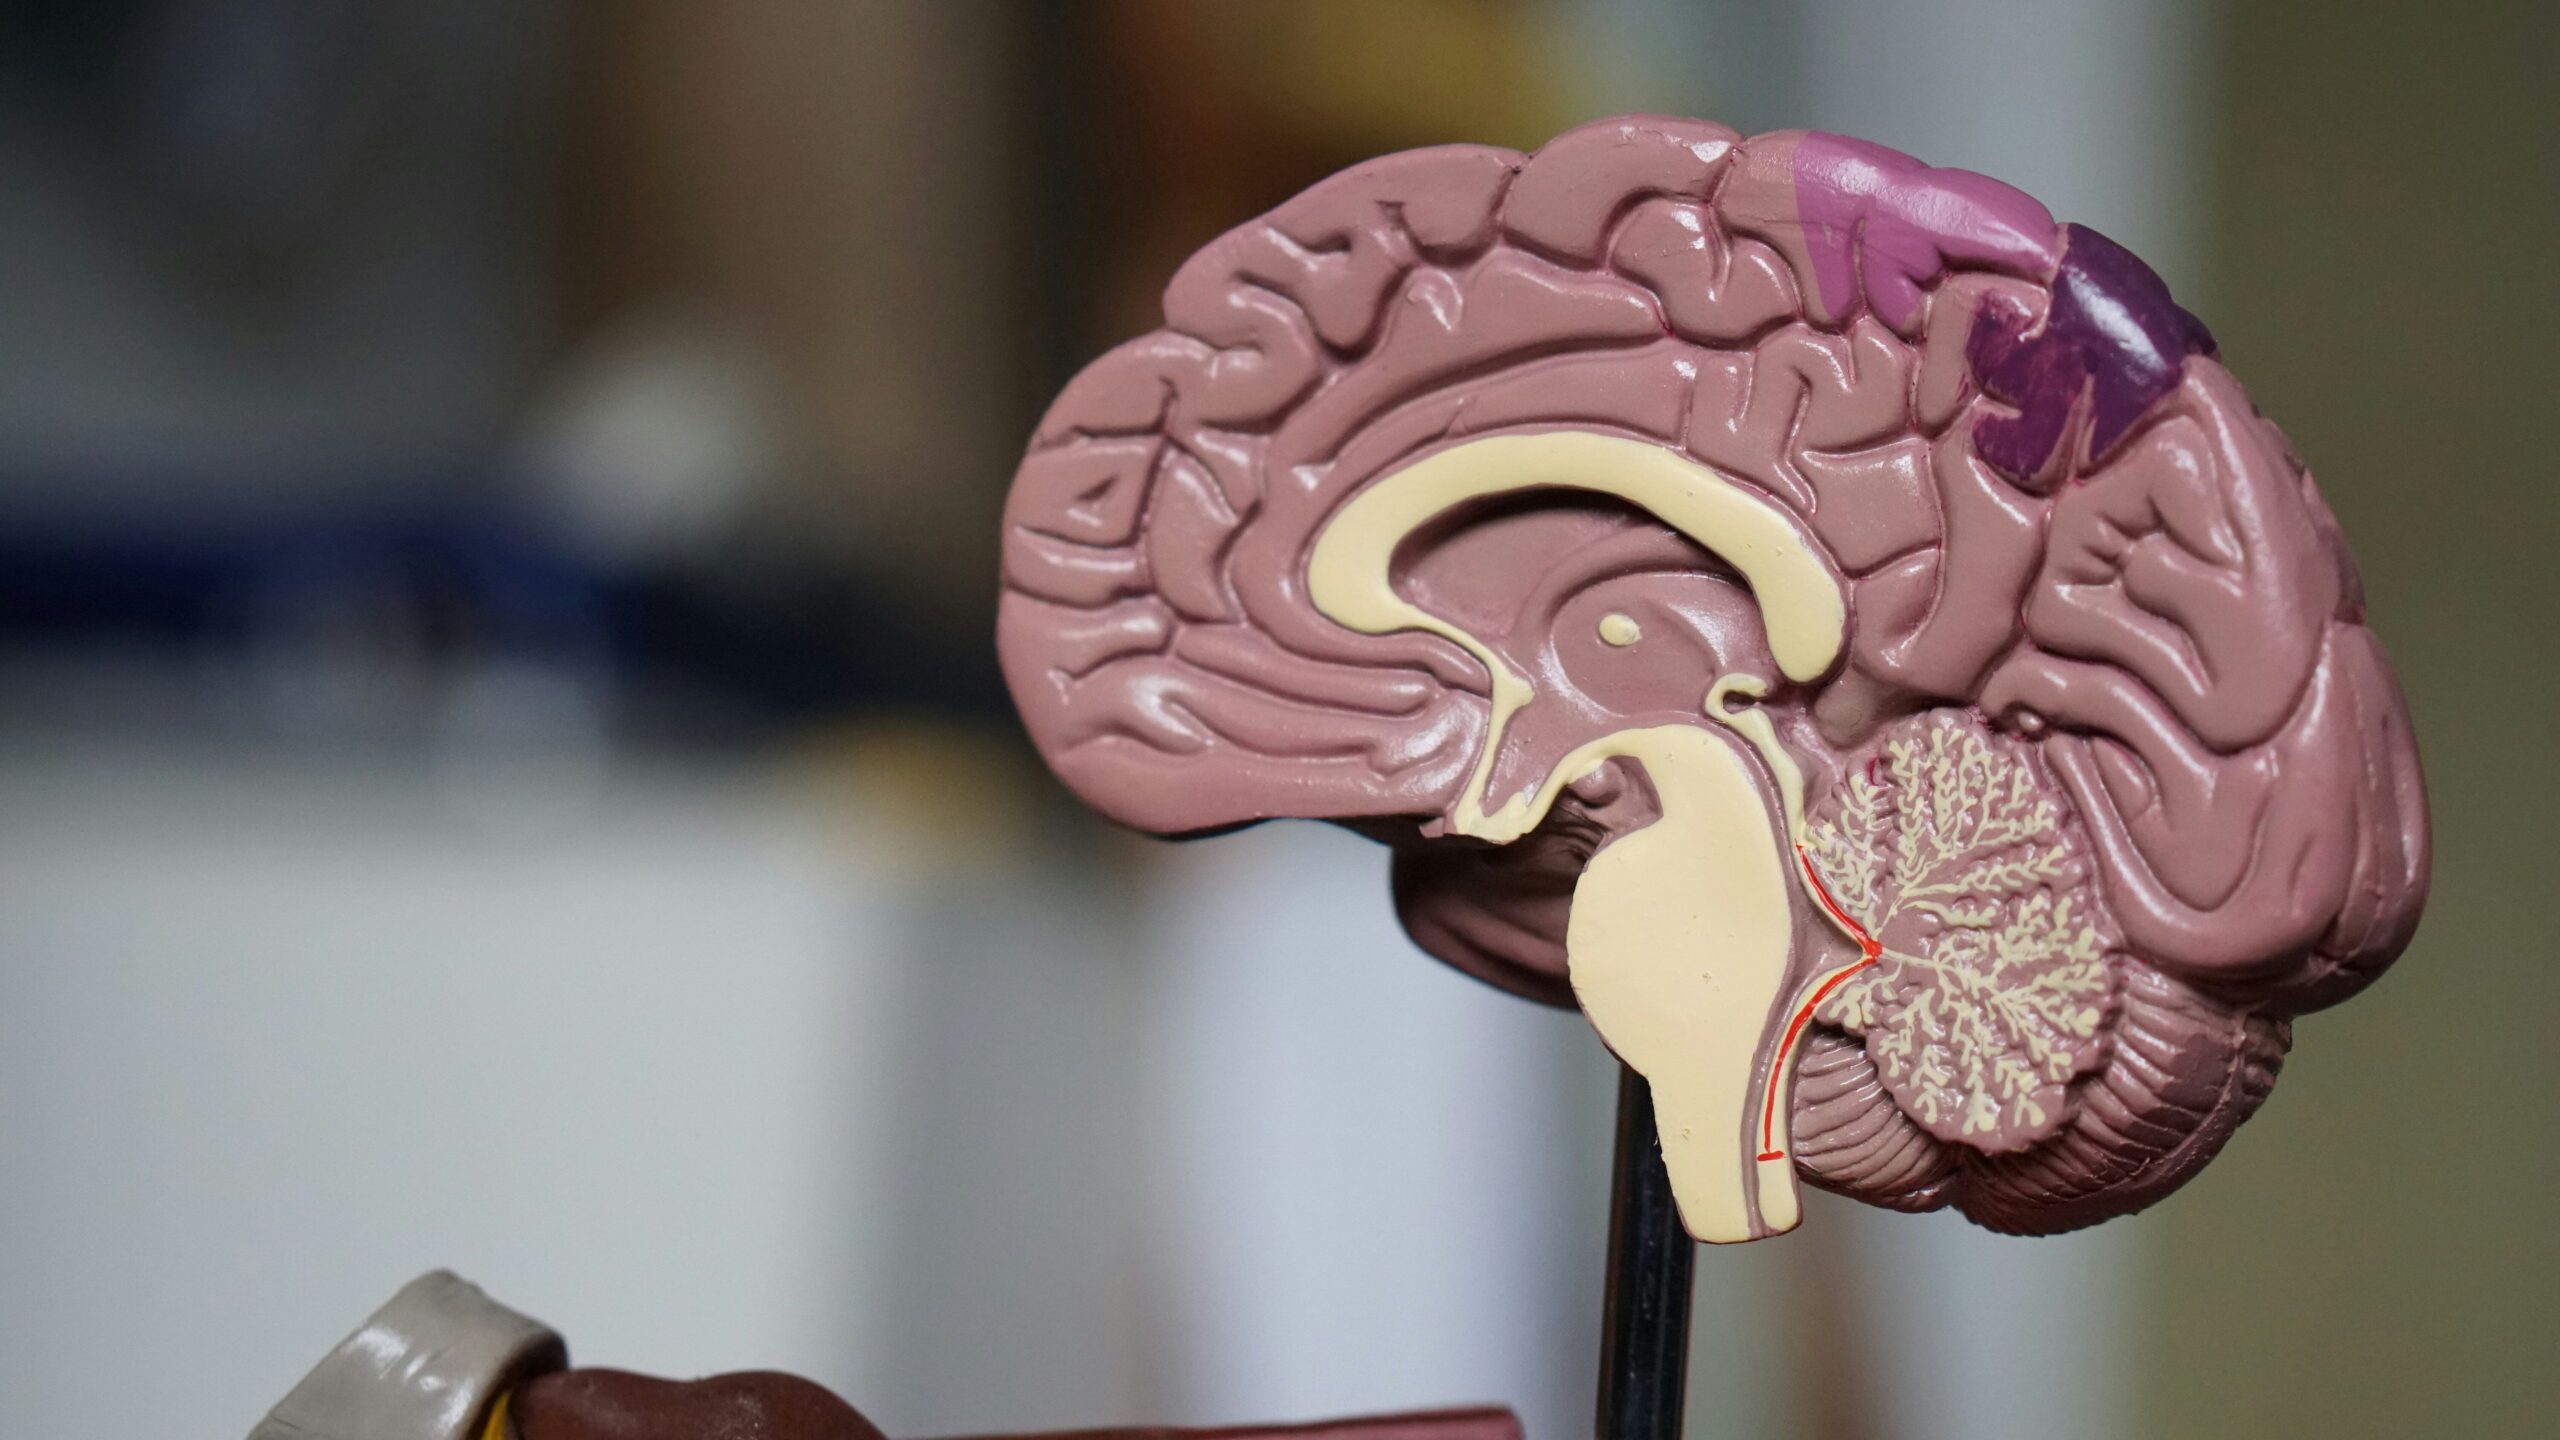

A recent study published in Nature Communications has revealed that the COVID-19 pandemic may have accelerated brain aging in individuals, regardless of whether they contracted the virus. Researchers found that the pandemic appears to have aged people’s brains by an average of 5.5 months, based on analyses of brain scans from nearly 1,000 healthy participants.

The research team utilized data from the UK Biobank, examining brain scans taken before and during the pandemic. By employing machine learning techniques and imaging data from over 15,000 brain scans, the scientists were able to predict the brain age of the participants. This analysis focused on comparable scans, ensuring participants were matched for gender, age, and health status.

Dr. Ali-Reza Mohammadi-Nejad, the study’s lead author, expressed surprise at the findings. “What surprised me most was that even people who hadn’t had COVID showed significant increases in brain aging rates,” he stated. This suggests that the pandemic’s broader impacts—such as isolation and uncertainty—may have negatively influenced brain health for many individuals.

The study did not delve into the specific reasons behind the observed acceleration in brain aging. However, the researchers indicated that men and those from socioeconomically disadvantaged backgrounds appeared to be affected more severely. They speculated that reduced social interaction and physical activity, alongside increased alcohol consumption during lockdowns, could contribute to these changes.

Dr. Dorothee Auer, a Professor of Neuroimaging and senior author on the study, emphasized the importance of environment in shaping brain health. “This study reminds us that brain health is shaped not only by illness, but by our everyday environment,” she said. “The pandemic put a strain on people’s lives, especially those already facing disadvantage. We can’t yet test whether the changes we saw will reverse, but it’s certainly possible, and that’s an encouraging thought.”

As the world begins to recover from the pandemic, these findings raise important questions about the long-term effects of social isolation and lifestyle changes induced by COVID-19. Understanding the potential for recovery and reversal of these changes will be crucial for public health strategies aimed at improving mental and cognitive health in the wake of this global crisis.